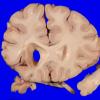

Infarct, Tract Degeneration, illustrative case (2)